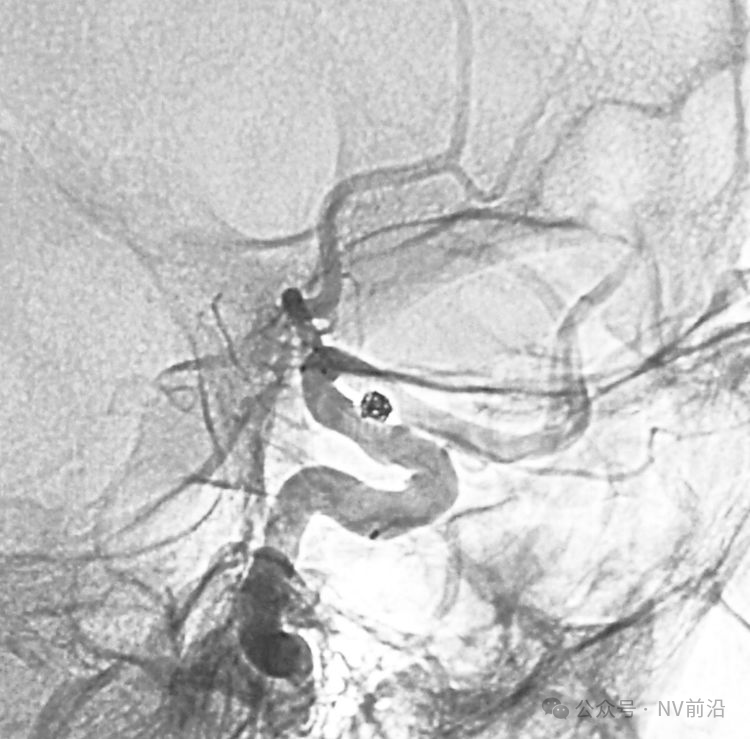

病例二,右侧椎动脉V4段夹层动脉瘤,以头痛入院,21个月前有SAH史。

右椎动脉造影三维重建

Echelon 10微导管头无论塑成C形还是S形,均无法稳定于动脉瘤腔内,遂使用回马枪技术,使微导管成襻通过,管头折返入瘤腔。

跨瘤颈释放Solitaire 4×20支架(蓝线),压住微导管(红线),在支架保护下经返折的微导管送入弹簧圈填塞瘤腔。